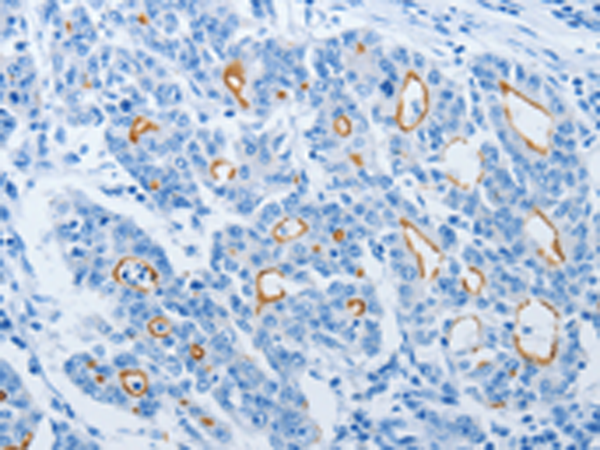

分类: 科研抗体货号: P04673别名: CGL3; PPH3; BSCL3; VIP21; MSTP085应用: WB,IHC反应种属: Human, Mouse, Rat